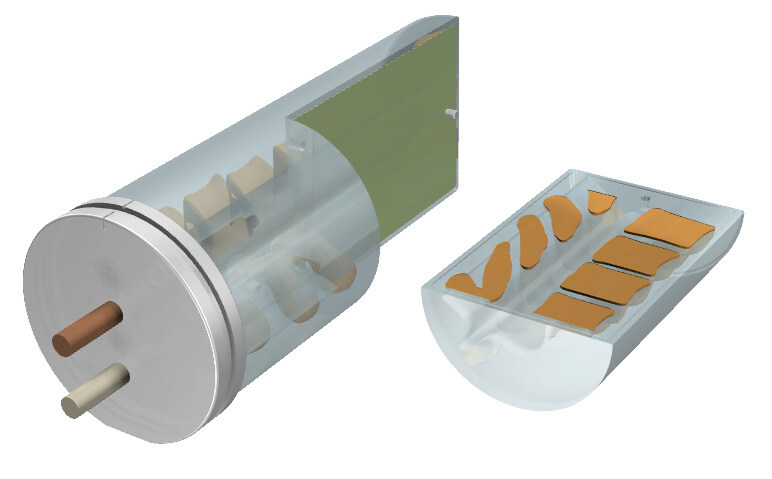

Linear attenuations of the simulated tissues are within 1% of actual attenuation for water and bone, and within 3% for lung from 50 keV to 15 MeV. The phantom contains a 3D anthropomorphic removable spine with cortical and trabecular bone as internal landmarks

Three OSL pockets in the right lung provide high-resolution dosimetry measurements to the target and spinal cord in a single delivery.

The removable split spine allows for film measurements in the sagittal orientation in the inferior half of the spine rod. Film can also be placed in the sagittal slice in the spine and lung inserts.